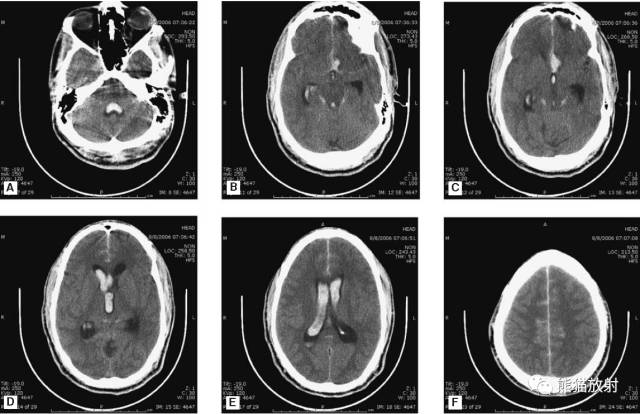

动脉瘤破裂导致蛛网膜下腔出血、脑室积血、非交通性脑积水。

与外伤性蛛网膜下腔出血不同,动脉瘤破裂导致的SAH常不累及大脑凸面,而位于基底池附近。脑动脉瘤常位于鞍上池的Willis环血管。

A:四脑室积血;B:中脑导水管、环池、右侧侧脑室颞角积血,前交通动脉处(动脉瘤好发位置)出血密度较高;C:三脑室积血;D-F:侧脑室积血,蛛网膜下腔出血(血液代替了脑脊液)。